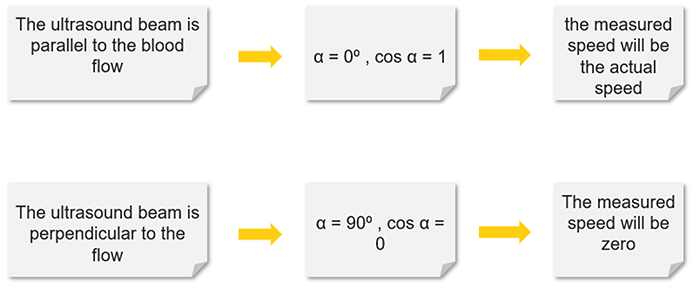

Effect of Angle

Note that the Doppler frequency also varies according to the angle alpha. The value of cosα varies with the angle from 0 to 1. When α = 0°, cosα = 1 and when α = 90°, cosα = 0.

For a constant flow velocity (V), the maximum value of cosα and therefore the highest value of the Doppler-shifted signal (δf) is at an angle of 0°. This corresponds to a Doppler beam which is parallel with the vessel, which can rarely be achieved in practice.

Theoretically, when α = 90° this means the blood flow is perpendicular to the Doppler beam, cosα = 0 and no Doppler-shifted signals will register.